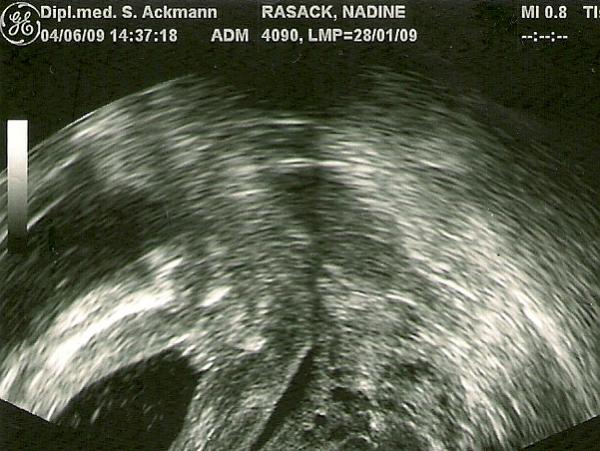

Also wirklich was erkennen kann ich da auch nix, aber da nix hängt würd ich auch sagen Mädel. Unser Outingbild sieht so aus, da kann die Kleine nix leugnen ;)